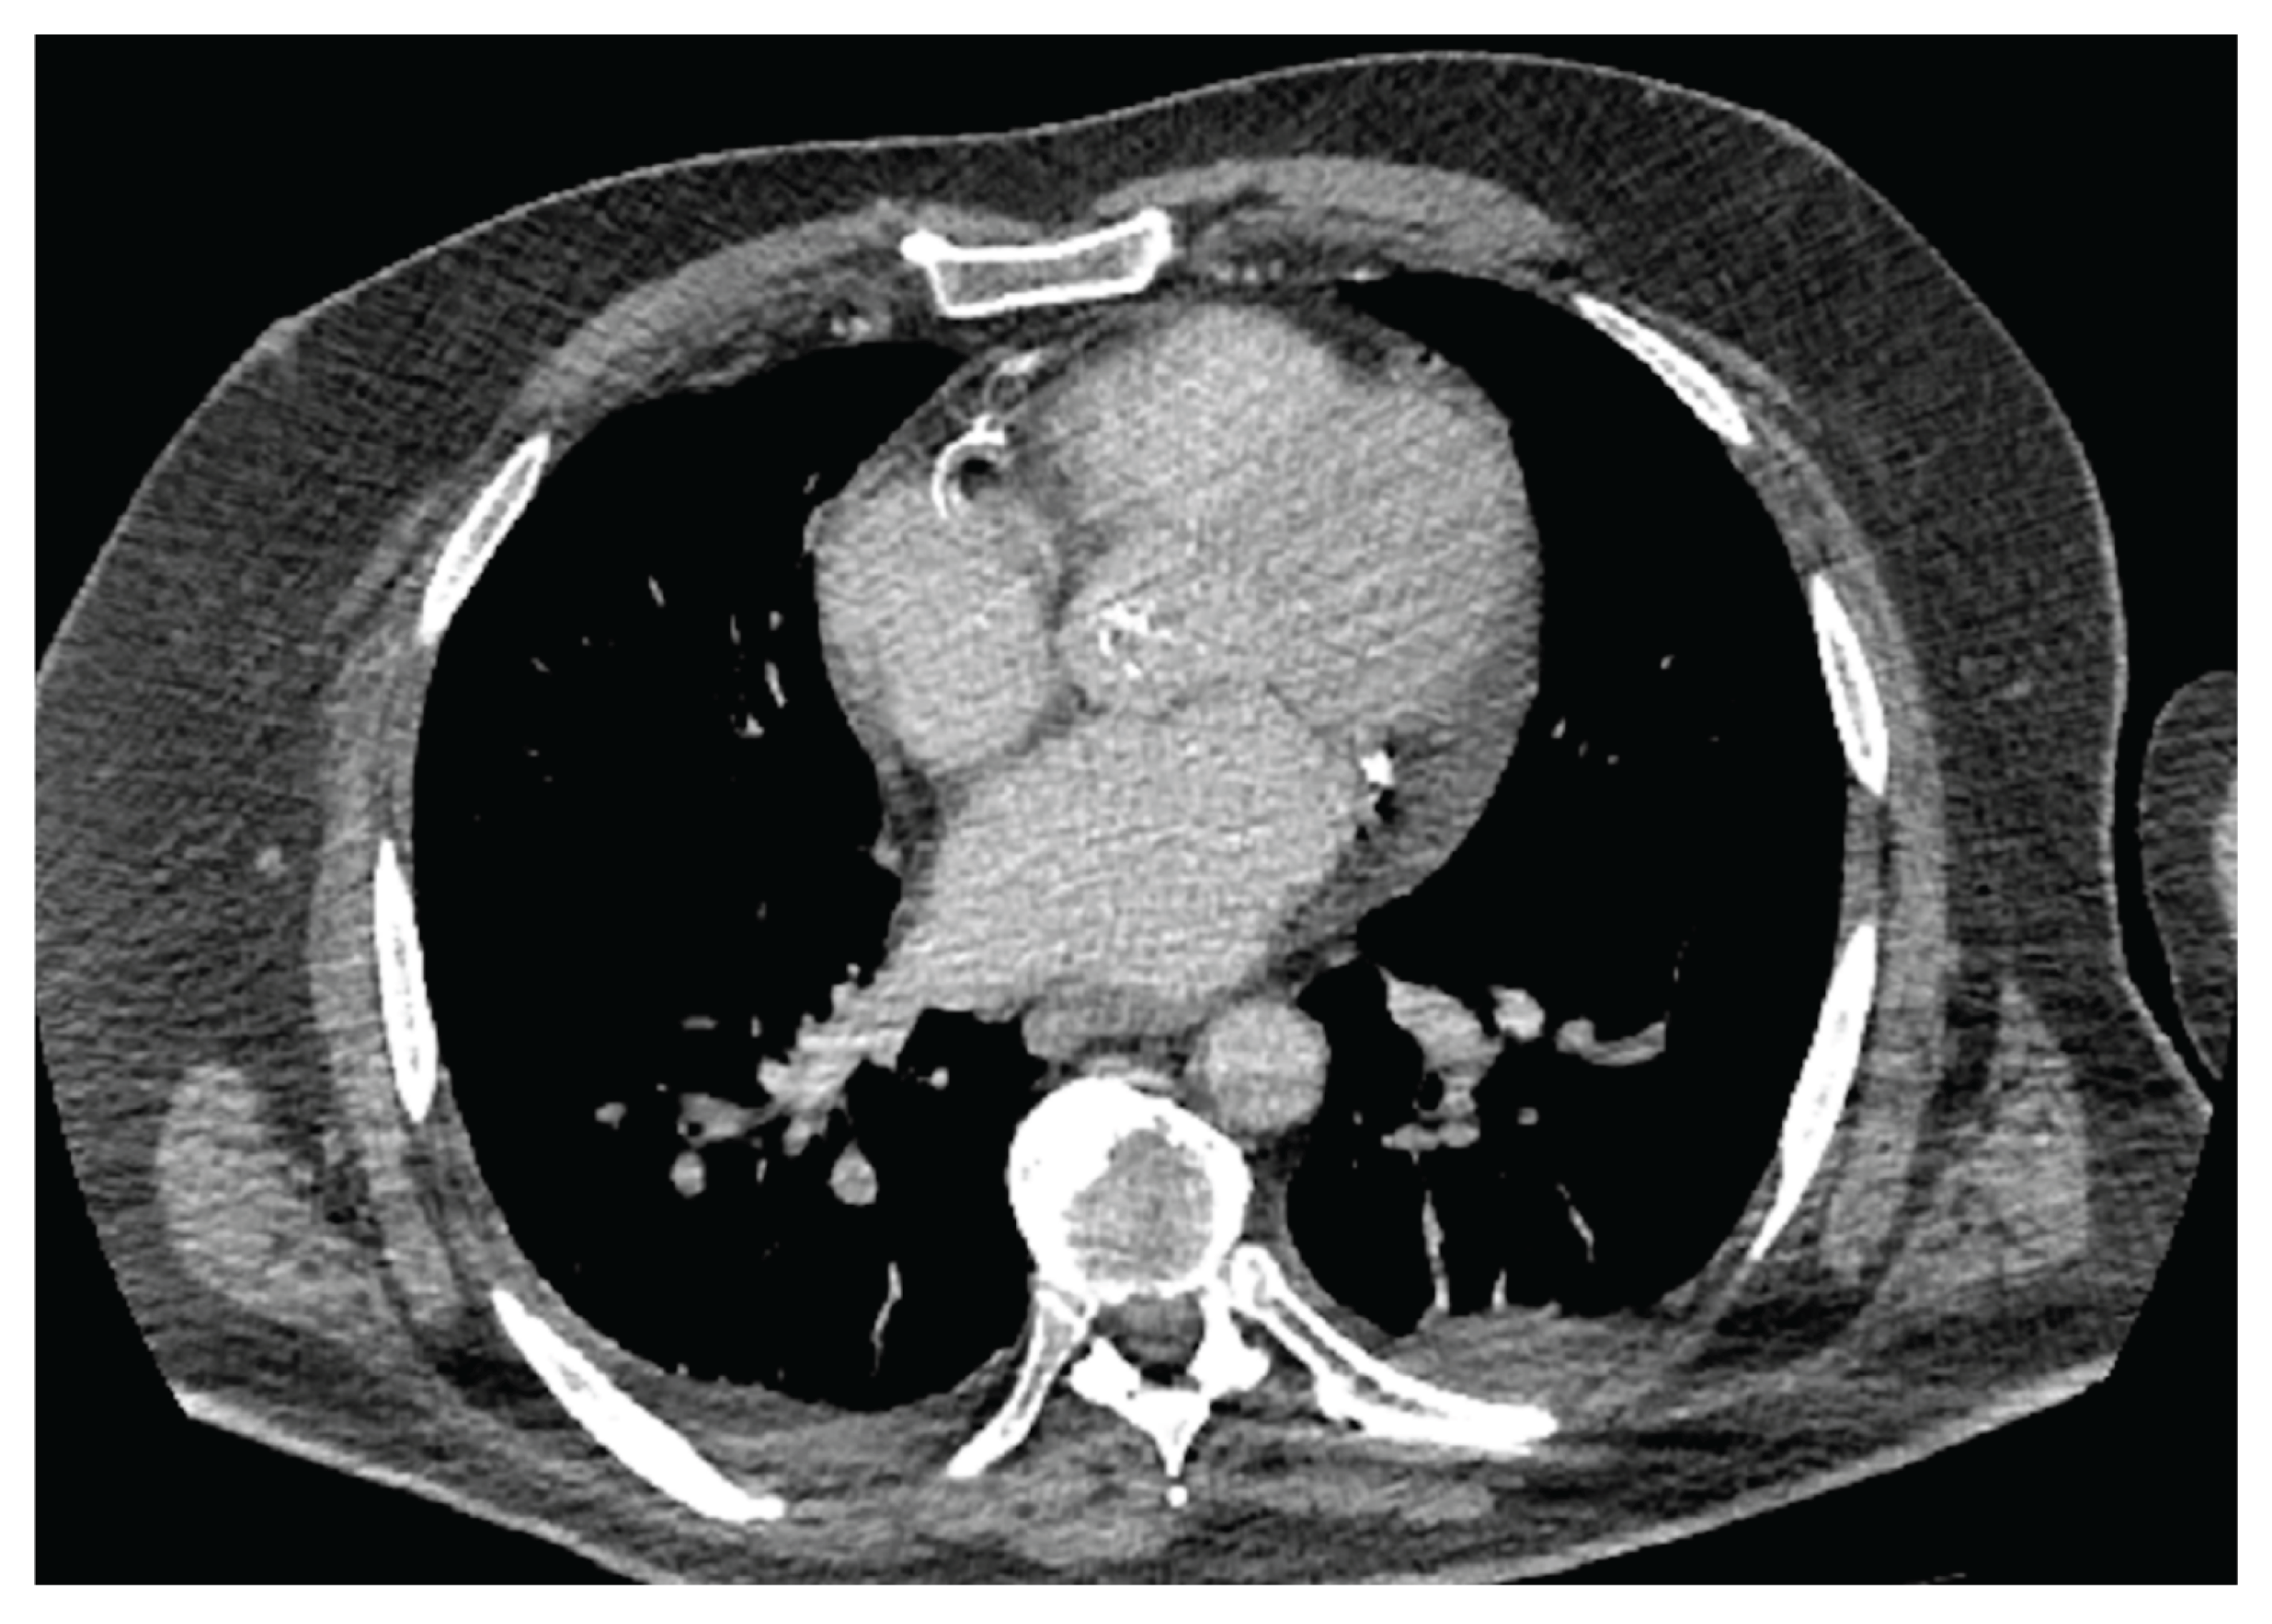

3. Cardiac CT and MRI in the Assessment of Epicardial Adipose Tissue

- Trimarchi, G; Carerj, ML; Zito, C; Bella, GD; Taverna, G; Cusmà Piccione, M; Crea, P; Lo Giudice, S; Buonpane, A; Bonanni, M; Restelli, D; Paradossi, U; Monteleone, A; Micari, A; Carerj, S. Epicardial Adipose Tissue: A Multimodal Imaging Diagnostic Perspective. Medicina (Kaunas) 2025, 61(6), 961. [Google Scholar] [CrossRef] [PubMed Central]

- West, HW; Siddique, M; Williams, MC; Volpe, L; Desai, R; Lyasheva, M; Thomas, S; Dangas, K; Kotanidis, CP; Tomlins, P; Mahon, C; Kardos, A; Adlam, D; Graby, J; Rodrigues, JCL; Shirodaria, C; Deanfield, J; Mehta, NN; Neubauer, S; Channon, KM; Desai, MY; Nicol, ED; Newby, DE; Antoniades, C; ORFAN Investigators. Deep-Learning for Epicardial Adipose Tissue Assessment With Computed Tomography: Implications for Cardiovascular Risk Prediction. JACC Cardiovasc Imaging 2023, 16(6), 800–816. [Google Scholar] [CrossRef] [PubMed] [PubMed Central]

- Umar, A; Hocking, J; Massin, SZ; Suszko, A; Wintersperger, BJ; Chauhan, VS. Association of Cardiac CT-Derived Epicardial Adipose Tissue With Atrial Fibrillation in Patients Without Left Atrial Fibrosis as Defined by Endocardial Voltage Mapping. J Cardiovasc Electrophysiol. 2025, 36(2), 489–500. [Google Scholar] [CrossRef] [PubMed]